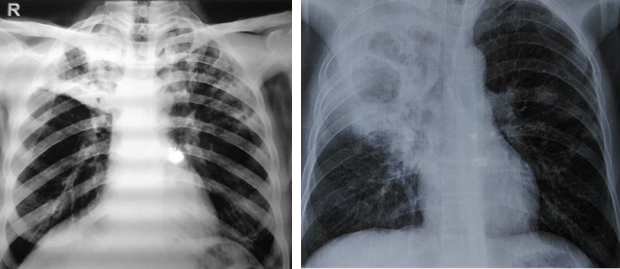

+ Xquang: thâm nhiễm lan toả hoặc tổn thương đông đặc rải rác 1 hay vài thuỳ phổi, thường gặp ở thuỳ trên, có thể kèm tràn dịch, tràn mủ màng phổi; hoặc tổn thương dạng hang áp xe

Viêm phổi: thường gặp nhất (50%)

+ vi khuẩn thâm nhập vào đường hô hấp theo đường máu đến là chủ yếu so với đường hít vào.

+ khởi phát là tình trạng ho khan hoặc kèm máu, sốt, khó thở, đau ngực kiểu màng phổi, có thể kèm các biểu hiện của tình trạng nhiễm khuẩn mạn tính như sụt cân, ra mồ hôi trộm.

+ viêm phổi thường không điển hình, ít khi có đau ngực hay có HC đông đặc như viêm phổi thuỳ